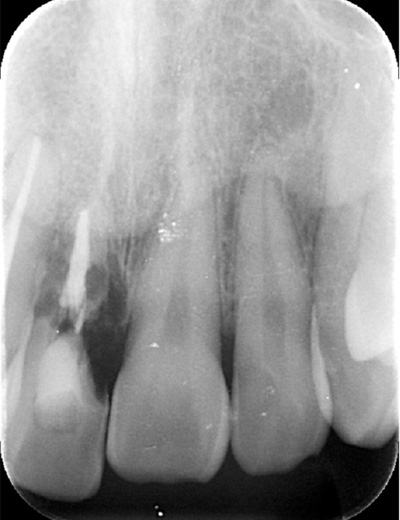

| 年代・性別 | 50代 男性 |

|---|---|

| 主訴 | 右下の歯が割れてしまったのでインプラントをして欲しい |

| 治療期間 | 約6ヶ月 |

| 費用 | 1,100,000円 |

| 治療内容 | インプラント、骨造成、結合組織移植、セラミック修復 |

| 治療に伴うリスク | インプラント周囲炎 セラミックの破折、脱離 |

*キャンセルポリシーをご一読のうえご予約ください